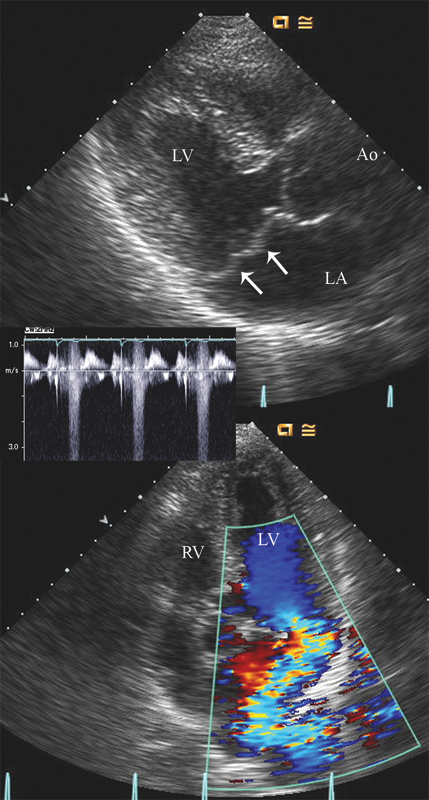

فحوصات تشخيصية لبعض امراض القلب والشرايين التاجية